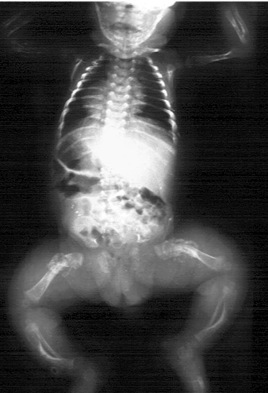

Achondroplasia

Achondroplasia aka disportionate dwarfism

C&C: gibbus deformity